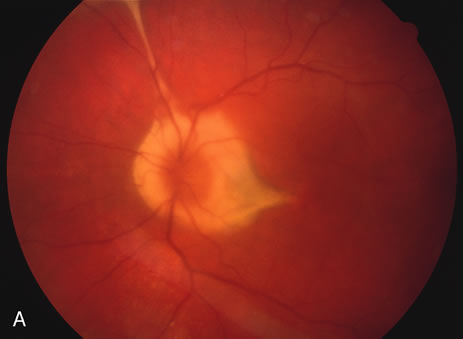

In the acute phase, the most common finding is the multiple creamy ovoid yellow-white patches that radiate out from the optic disc and are approximately one half to three fourths disc diameter in size and with indistinct borders. With time these lesions may atrophy and coalesce causing large areas of chorioretinal atrophy. There may be cystoid macular edema and retinal vasculitis as well. Some cases may also develop choroidal neovascularization, epiretinal membranes, macular holes or cataracts (Fig. 19).

Fig. 19. Vitiliginous lesions radiating from the posterior pole to the periphery. Note they are subtle with indistinct edges.